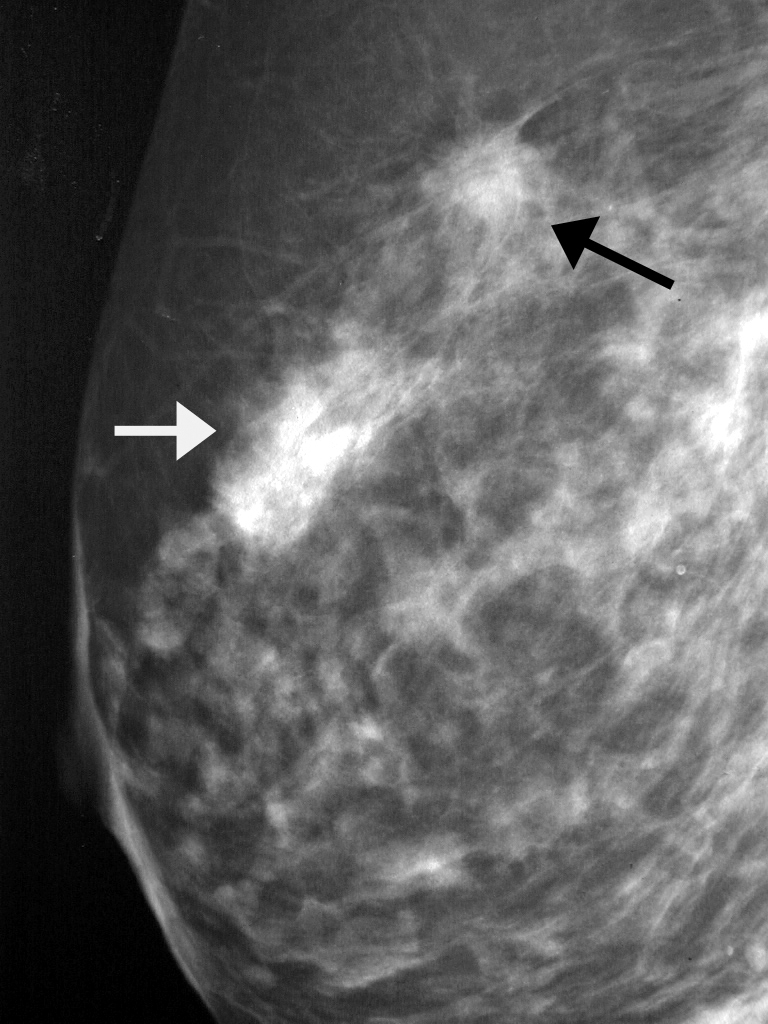

Феномен гипердиагностики в маммографии: примеры и иллюстрации

Раздел: Образы вокруг